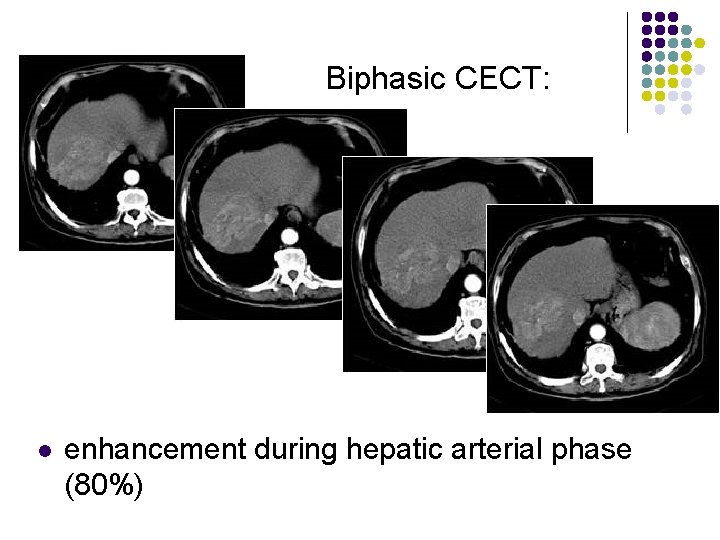

Biphasic CECT: l l l enhancement during hepatic arterial phase (80%) decreased attenuation during portal venous phase with inhomogeneous areas of contrast accumulation isodensity on delayed scans (10%) thin contrast-enhancing capsule (50%) due to rapid washout wedge-shaped areas of decreased attenuation (segmental/lobar perfusion defects due portal vein occlusion by tumor thrombus)

Biphasic CECT: l enhancement during hepatic arterial phase (80%)

Biphasic CECT: l enhancement during hepatic arterial phase (80%)